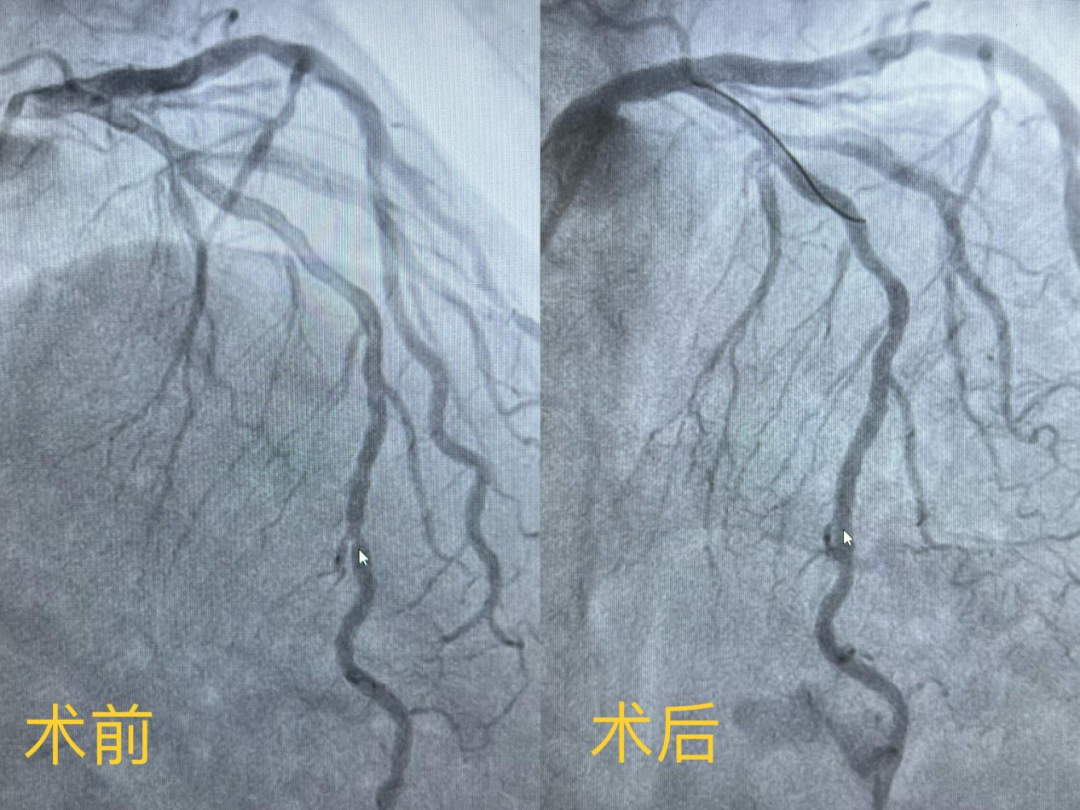

女性患者,因反復胸痛10余年就診我院,心內(nèi)科團隊為其行冠狀動脈造影確診冠心病,左前降支遠段中部90%狹窄,需要行冠脈支架植入治療。在與患者及家屬溝通時,患者家屬提到,他們了解得知臨床有一種新型的可吸收支架,植入體內(nèi)后支架能完全被降解和吸收,希望能用這種新型的支架進行手術治療。由于生物可吸收支架有著嚴格的適應癥,心內(nèi)科醫(yī)護團隊經(jīng)過嚴格篩選評估及反復討論后制定了詳細的手術方案,為該患者冠狀動脈狹窄處精準植入一枚生物可吸收支架,手術過程順利,術后造影顯示支架釋放貼壁良好,無殘余狹窄,患者胸悶痛癥狀完全消失,術后3天順利出院。

(手術前后造影圖)